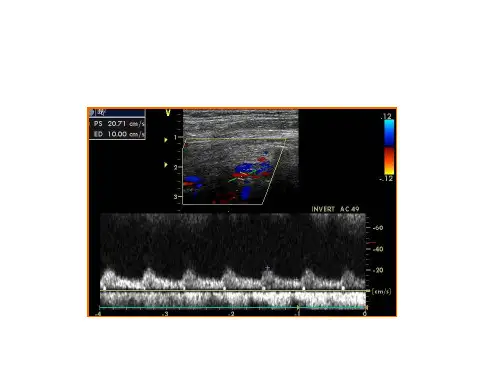

目前常用的超声检查方法主要包括超声多普勒和彩色多普勒。

超声多普勒检查可以测量椎动脉的流量速度和血流峰值,可以反映出动脉管壁厚度和直径的变化,进而判断是否存在狭窄。

具体的诊断标准如下:1.椎动脉的峰值血流速度:该指标是判断椎动脉狭窄程度的主要指标之一。

通常认为在正常情况下,椎动脉的峰值血流速度应该小于60cm/s。

一旦该指标超过了60cm/s,就需要进一步确认是否存在狭窄。

2.椎动脉的流量变化:这是反映狭窄程度的另一个重要标志。

在狭窄的情况下,椎动脉的流量将显著降低。

通常情况下,正常情况下椎动脉的流量应该在100-200ml/min之间。

超声是一种非常常见的检查方式,可用于对椎动脉狭窄进行诊断,其常用的诊断标准包括以下几个方面:1.流速参数:超声检查时可以通过测量椎动脉内血流的速度和流量参数,来评估其狭窄的程度。

常用的流速参数包括收缩期峰值流速(PSV)和舒张期末流速(EDV),以及两者之间的比值(PSV/EDV)。

一般来说,PSV大于50cm/s、EDV大于20cm/s、PSV/EDV比值大于3均可提示椎动脉狭窄存在。